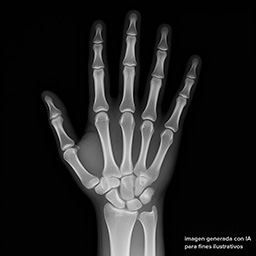

Ejemplo Radiografía de Mano o Carpo

imagen referencial con fines didácticos

La radiografía de mano, también conocida como radiografía de carpo, es un estudio radiológico utilizado principalmente para evaluar la edad ósea en niños y adolescentes. Esta imagen muestra los huesos de la mano y muñeca, siendo fundamental en ortodoncia interceptiva, endocrinología pediátrica y seguimiento del crecimiento.